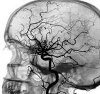

Ангиография сосудов головного мозга (церебральная ангиография). Метод обследования - рентгенологическое исследование сосудистой сети головного мозга после введения контрастного вещества в кровь. Контраст позволяет изучать структурные особенности кровеносных сосудов и выявлять патологические отклонения в кровоснабжении тканей головного мозга. Ангиография сосудов головного мозга назначается при подозрении на аневризмы и артериовенозные мальформации. Это позволяет оценить характеристики кровообращения в разных частях мозга, определить местонахождение стриктур и окклюзий сосудов. Исследование также используется в диагностике объемных образований.

Этот метод используется для выявления цереброваскулярной патологии, выявления аномального развития сосудов, их чрезмерной извилистости или образования петель, сужения света, закупорки, асимметрии в разрядах сосудистых ветвей, аневризм, пороки развития сосудов. Церебральная ангиография позволяет определить степень, распространенность и локализацию сосудистых нарушений, изучить состояние кровообращения в сосудистых коллатералях (отвести сосудистые пути), оценить кровоток венозного выхода. Своевременная диагностика сосудистой патологии может предотвратить развитие острых нарушений кровообращения - ишемии и кровоизлияний. Кроме того, ангиография применяется при опухолях полушарий и области седла. На онкологический процесс в ткани головного мозга указывает местное смещение артерий и вен, наличие новообразованных сосудов (превращение в опухоль).